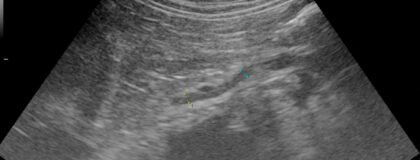

In diesem vetinar werden die Grundlagen der Sonographie der Nebennieren bei Hund und Katze vermittelt. Dabei liegt der Fokus auf der korrekten Beurteilung von Normalbefunden sowie der Identifikation häufiger und relevanter Pathologien. Die Teilnehmer:innen lernen, wie die Nebennieren in der Ultraschalldiagnostik dargestellt werden, welche Variationen im Normalbereich existieren und wie typische Erkrankungen wie Hyperadrenokortizismus (Cushing-Syndrom), Nebennieren-Tumoren oder Nebenniereninsuffizienz erkannt werden können. Zudem werden praxisorientierte Tipps zur optimalen Bildgebung und zur Interpretation der Ultraschallbefunde gegeben. Das Webinar richtet sich an Tierärzt:innen, die ihre Kenntnisse in der sonographischen Diagnostik der Nebennieren vertiefen möchten.